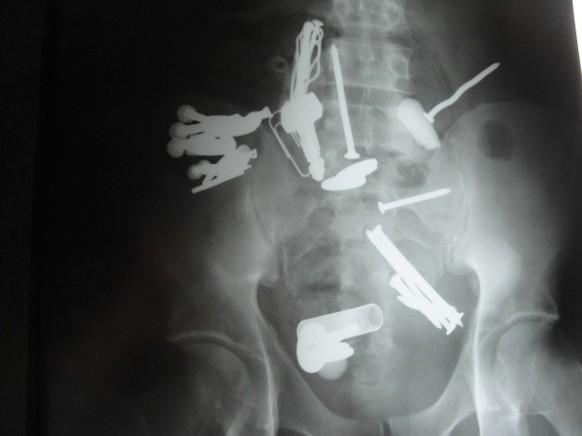

Wenn sich jemand einen Vibrator in den Po steckt, sollte dieser Jemand nicht versuchen, ihn mit Salatbesteck wieder herauszubekommen. Dieses bleibt nämlich auch stecken.

Schlüssel verloren? Such mal hinten.

Zu dunkel? Nimm eine Taschenlampe!